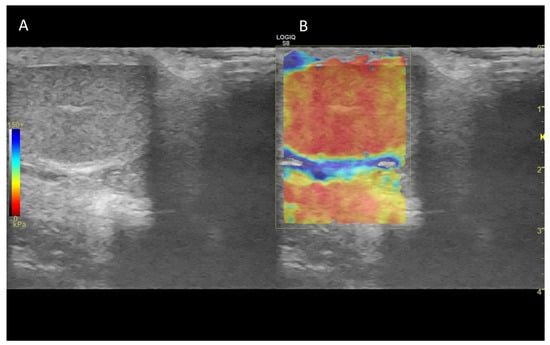

7. Ultrasound Elastography

7.1. Technology and Applications

7.2. Normal Findings

7.3. Abnormal Findings